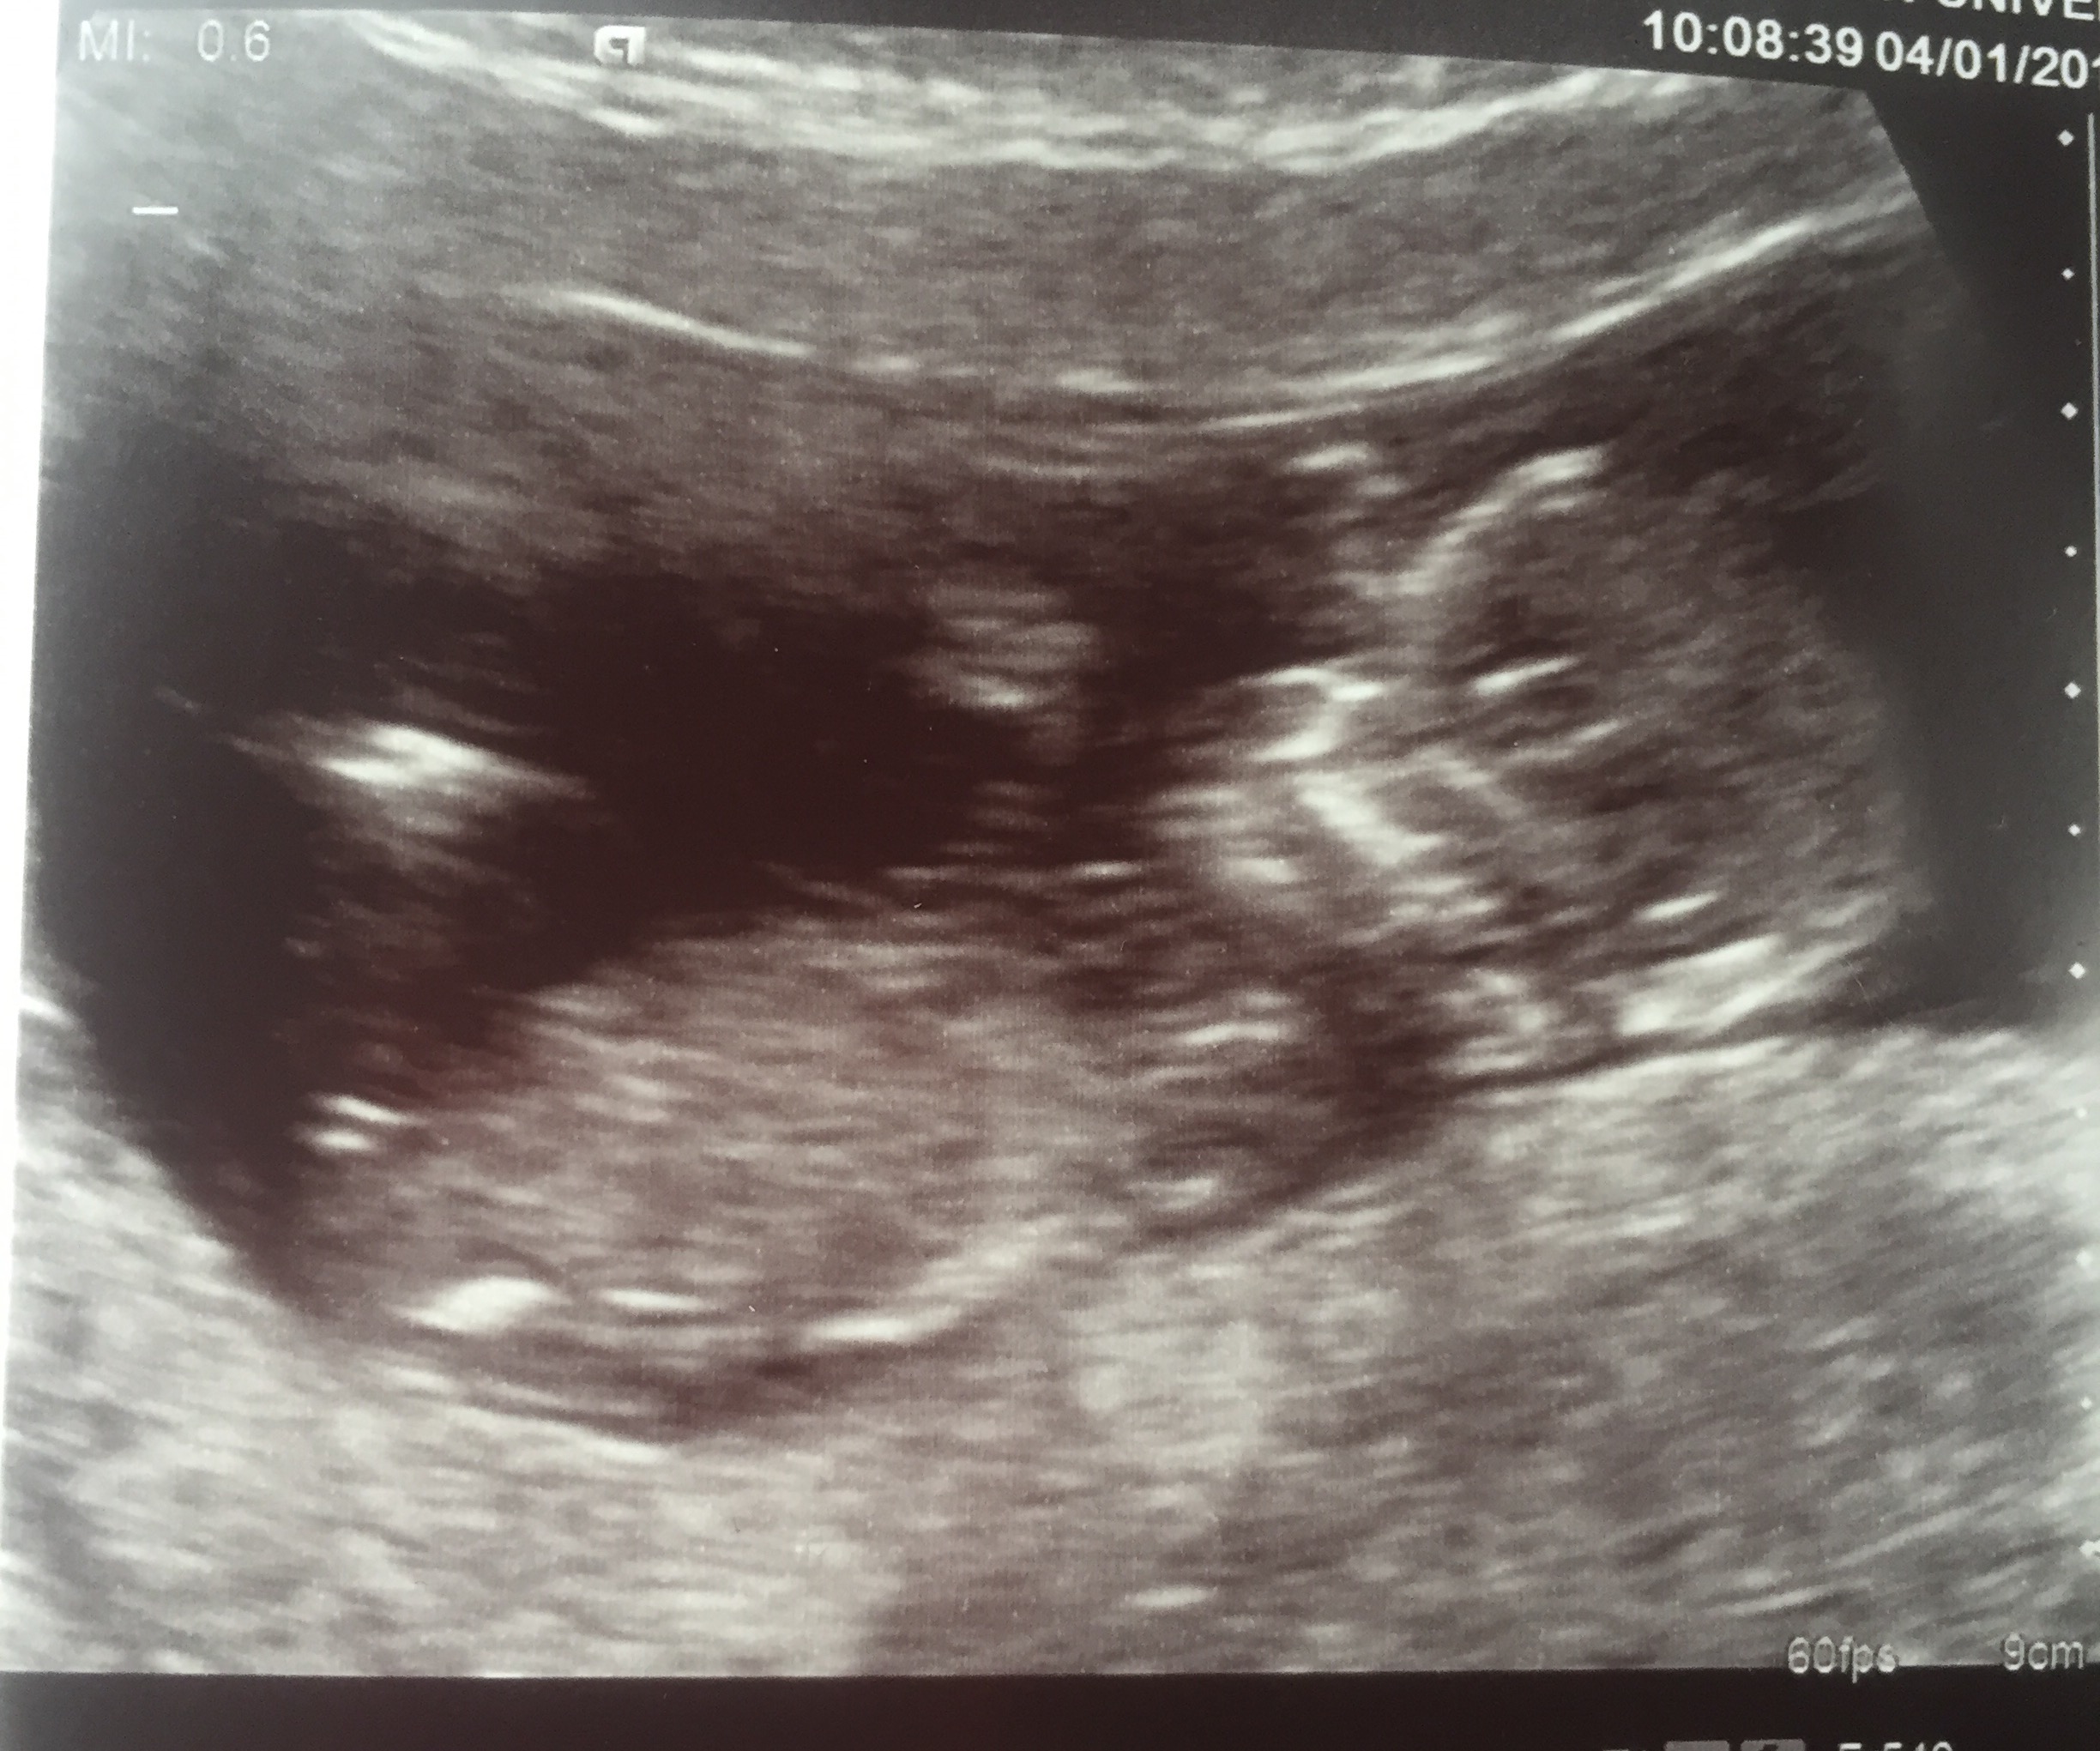

12+2 weeks scan pic.Attachment 38547

A little early for nub guessing but leaning girl.

Leaning boy